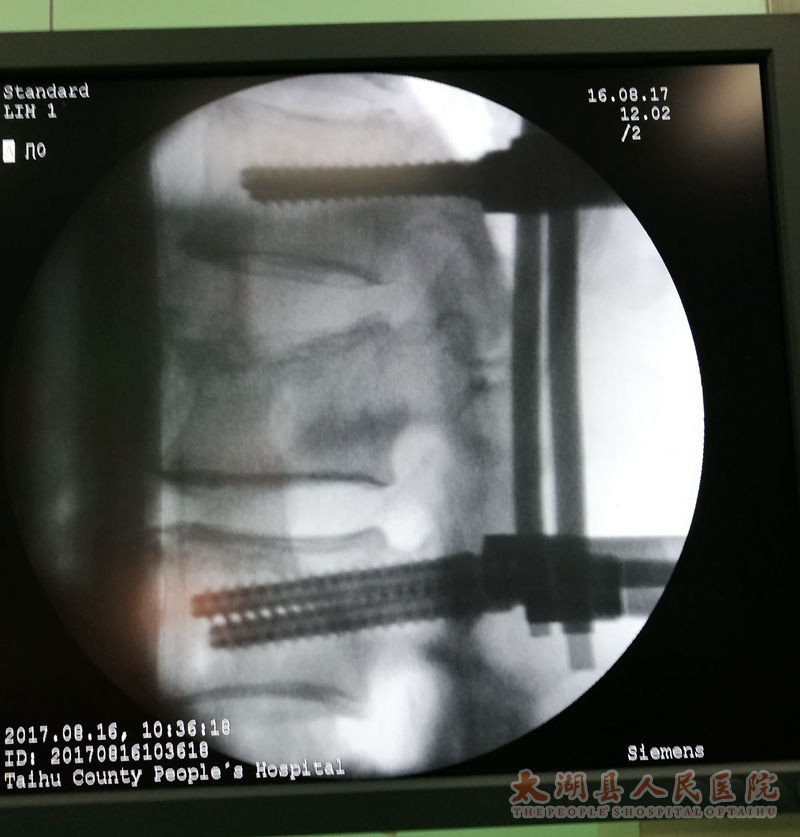

2017816日,医院骨一科郑效珍技术团队为一腰椎椎体压缩性骨折患者实施微创小切口脊柱后路钉棒系统内固定术取得圆满成功,作为县医院2016年批复的25项新技术新项目之一,此项手术的成功开展标志着该院在微创内固定领域又取得一项重大技术突破,拓宽了我县骨科微创手术范畴,填补了我县脊柱微创内固定领域空白。

患者朱先生,山东日照人,61岁,因高处坠落而入院,诊断为“腰1椎体压缩性骨折”,手术指征明确,术前检查无明显手术禁忌。患者要求采用最好的手术方式治疗,为了最大限度减少对患者的创伤,加快其康复,术前科室进行认真讨论,查阅资料,观看手术视频,制订详细的手术计划,并于816日在全麻下行微创小切口脊柱后路钉棒系统内固定术治疗腰1椎体压缩性骨折,术后复查X线提示腰椎高度恢复,内固定位置正常,术后3周即可下床活动。

医院副院长兼骨科主任郑效珍介绍,传统椎弓根内固定术采用切开皮肤,剥离肌肉,显露椎体结构后,植入椎弓根螺钉固定,存在创伤大(约10厘米)、椎旁肌肉剥离广泛、术中出血多(一般出血约300多毫升)、术后切口引流量大(一般约200多毫升)、术后切口疼痛、恢复期长等。而微创经皮椎弓根钉棒内固定植骨融合术因其手术创伤小(约2厘米),术中出血少(约20毫升),不剥离椎旁肌肉,术后切口无需引流,无术后切口疼痛,可早期下地进行功能恢复,是近年来发展起来的新技术,也是目前微创治疗腰椎滑脱、胸腰椎骨折、椎管狭窄、肿瘤等脊柱疾病的一种先进手术方式。经皮椎弓根钉棒系统内固定术要求很高,因为是微创技术,对手术技术要求比传统手术方式更高,术前需要非常周密的计划,根据患者的影像资料做非常精确地测量和定位,更需要手术医生具有非常娴熟的开放椎弓根钉棒系统内固定技术及经皮椎弓根穿刺技术。